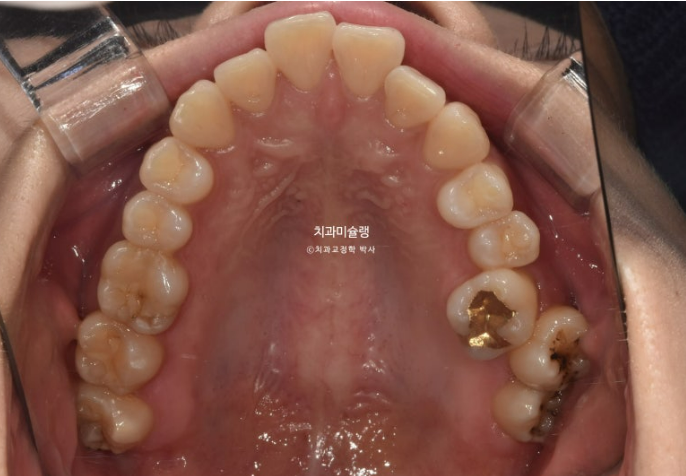

입매는 앞니 돌출때문에 약간의 입술부전증이 있지만 입을 다물기 힘들정도의 심한 돌출은 아니며 환자분도 비발치 계획을 더 선호했습니다.

치료계획은 사랑니 모두 발치하고 어금니들을 사랑니 공간으로 밀어내어 돌출을 해소하는 비발치 돌출입 교정입니다.

인비절라인 선택하셨고 치료들어갔습니다.